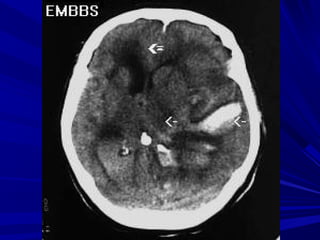

Phát hiện xuất huyếtPhát hiện xuất huyết

Xuất huyết là các vùng tăng đậm độ và có thể thấyXuất huyết là các vùng tăng đậm độ và có thể thấy

trong các bệnh lý:trong các bệnh lý:

Tụ máu ngoài màng cứng,Tụ máu ngoài màng cứng,

Tụ máu dưới màng cứngTụ máu dưới màng cứng

Xuất huyết màng nãoXuất huyết màng não

Xuất huyết não thấtXuất huyết não thất

Xuất huyết trong nãoXuất huyết trong não

Phân biệt hoá vôi và xuất huyết nhỏ vùng nhân nềnPhân biệt hoá vôi và xuất huyết nhỏ vùng nhân nền

Phân biệt xuất huyết cầu não với hình ảnh nhiễuPhân biệt xuất huyết cầu não với hình ảnh nhiễu